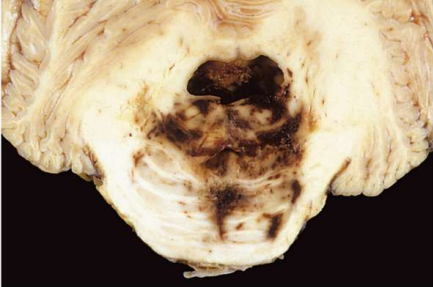

38

What is **spontaneous intracerebral** haemorrhage (stroke) caused by?

**Hypertension- 60 years +, rupture of small intraparenchymal blood vessels** Cerebral amyloid angiopathy Arteriovenous and cavernous malformations Tumours

39

What sites are commonly affected by spontaneous intracerebral haemorrhages?

Basal ganglia Thalamus Pons Cerebellum

40

What are the complications of spontaneous intracerebral haemorrhages?

Accumulation of hamorrhage leads to raised ICP Raised ICP causes midline shift and compression of adjacent brain parenchyma